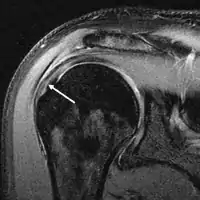

MRI

Magnetic resonance imaging (MRI) and ultrasound[42] are comparable in efficacy and helpful in diagnosis although both have a false positive rate of 15 - 20%.[43] MRI can reliably detect most full-thickness tears although very small pinpoint tears may be missed. In such situations, an MRI combined with an injection of contrast material, an MR-arthrogram, may help to confirm the diagnosis. It should be realized that a normal MRI cannot fully rule out a small tear (a false negative) while partial-thickness tears are not as reliably detected.[44] While MRI is sensitive in identifying tendon degeneration (tendinopathy), it may not reliably distinguish between a degenerative tendon and a partially torn tendon. Again, magnetic resonance arthrography can improve the differentiation.[44] An overall sensitivity of 91% (9% false negative rate) has been reported indicating that magnetic resonance arthrography is reliable in the detection of partial-thickness rotator cuff tears.[44] However, its routine use is not advised, since it involves entering the joint with a needle with potential risk of infection. Consequently, the test is reserved for cases in which the diagnosis remains unclear.

Diagnostic modalities, dependent on circumstances, include X-ray, MRI, MR arthrography, double-contrast arthrography, and ultrasound. Although MR arthrography is currently considered the gold standard, ultrasound may be most cost-effective.[31] Usually, a tear will be undetected by X-ray, although bone spurs, which can impinge upon the rotator cuff tendons, may be visible.[32] Such spurs suggest chronic severe rotator cuff disease. Double-contrast arthrography involves injecting contrast dye into the shoulder joint to detect leakage out of the injured rotator cuff[33] and its value is influenced by the experience of the operator. The most common diagnostic tool is magnetic resonance imaging (MRI), which can sometimes indicate the size of the tear, as well as its location within the tendon. Furthermore, MRI enables the detection or exclusion of complete rotator cuff tears with reasonable accuracy and is also suitable to diagnose other pathologies of the shoulder joint.[34]